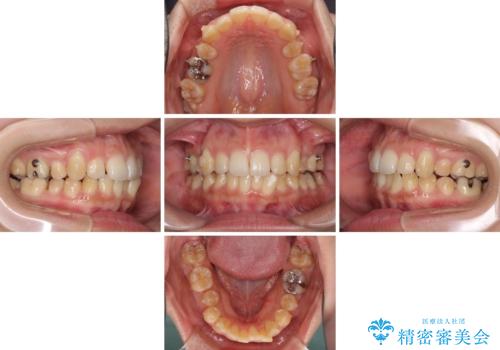

- 下の前歯のデコボコを気にして来院された患者様です。

来院当初、上顎の八重歯は気にしていらっしゃらなかったのですが、矯正治療をするのであれば、しっかりと治した方が良いと説明し、全顎矯正を行うこととしました。

八重歯の移動量が多く、インビザライン単体での治療は困難と判断し、補助装置により八重歯移動後にインビザラインを用いることとしました。